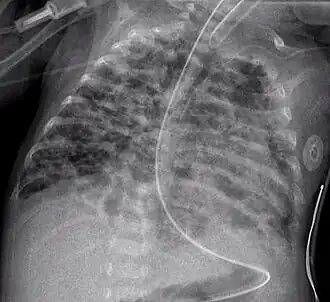

Röntgenopname van longen met bronchopulmonale dysplasie

Bronchopulmonale dysplasie (BPD) is een longaandoening die werd veroorzaakt door langdurige beademing. Veelal ontstaat BPD bij prematuur geboren kinderen die langdurig extra zuurstof nodig hebben.[1] Om het risico op BPD zo klein mogelijk te houden zal beademing alleen zo kort mogelijk en als het echt niet anders kan worden toegepast.